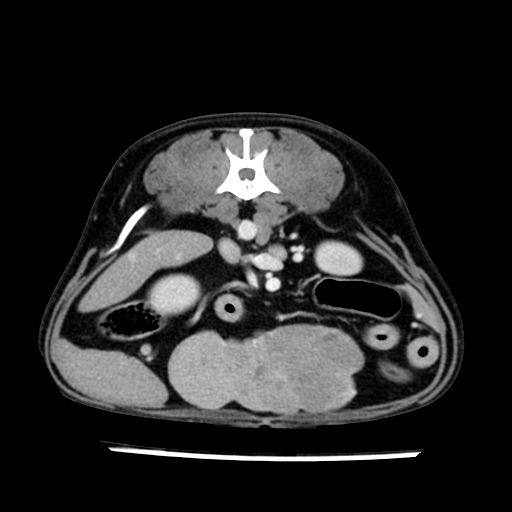

prescritto esame TAC

sequenza immagini limitata al fegato reni e surreni

le immagini ecografiche rispetto alla tac datano circa 7 mesi prima ,le surrenali sono normali nonostante il test acth sia risultato positivo .all’esame TAC dopo diversi mesi risultano aumentate armonicamente nel volume e si individua un forte sospetto di adenoma ipofisario .

sospetto adenoma ipofisario vs. meno probabilmente meningioma della base; intertiziopatia polmonare; lesione espansiva epatica, verosimilmente del lobo laterale sinistro, di sospetta natura neoplastica; lesioni spleniche di natura da definire; iperplasia/ipertrofia delle ghiandole surrenali, bilateralmente; vertebra di transizione del rachide toracico; tenosinovite cronica del muscolo bicipite brachiale di destra.